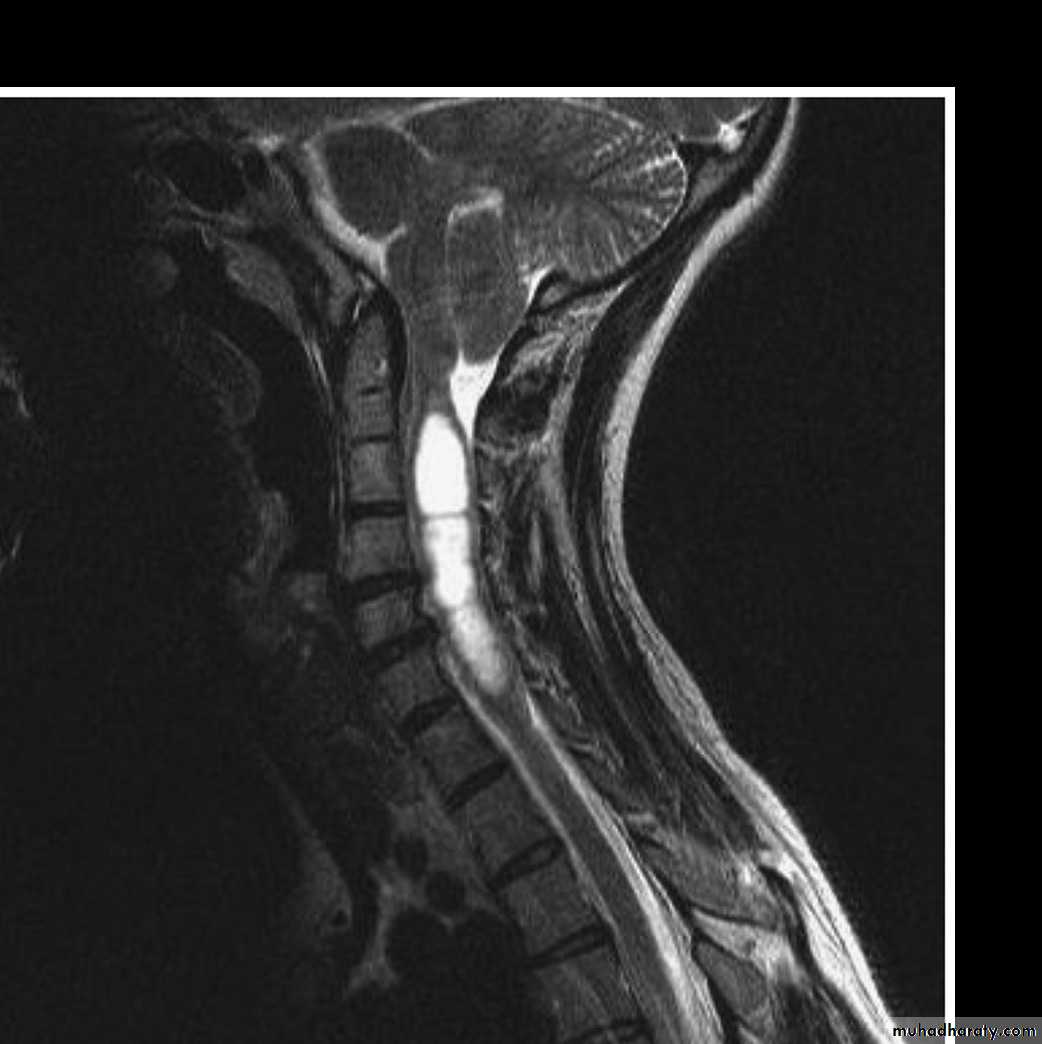

Syringomyelia:

Syringomyelia is a cystic dilation or fluid-filled cavity within the spinal cord that typically involves the cervical region, but may extend up into the brainstem or down to the conus.Causes:

1-congenital.2-trauma.

3-tuomr.

4-spinal cord infarction.

5-infection .

Clinical Features:

1-Clinical symptoms follow the destructive path of the widening syrinx, which begins in the center and expands outward and longitudinally(central cord syndrome).2-flaccid weakness in lower cervical segments and corticospinal tract changes in the legs.

3-loss of pain and temperature sensation occurs in a capelike distribution due to injury of the decussating spinothalamic tract fibers.

4-the dorsal column still spared till late stage.

Investigations:

1-MRI of cervicothoracic spine with contrast is the investigation of choice which show cystic area filled with CSF.

2- MRI of brain and lumbosacral area should be done also to exclude chiari malformation and spina bifida.